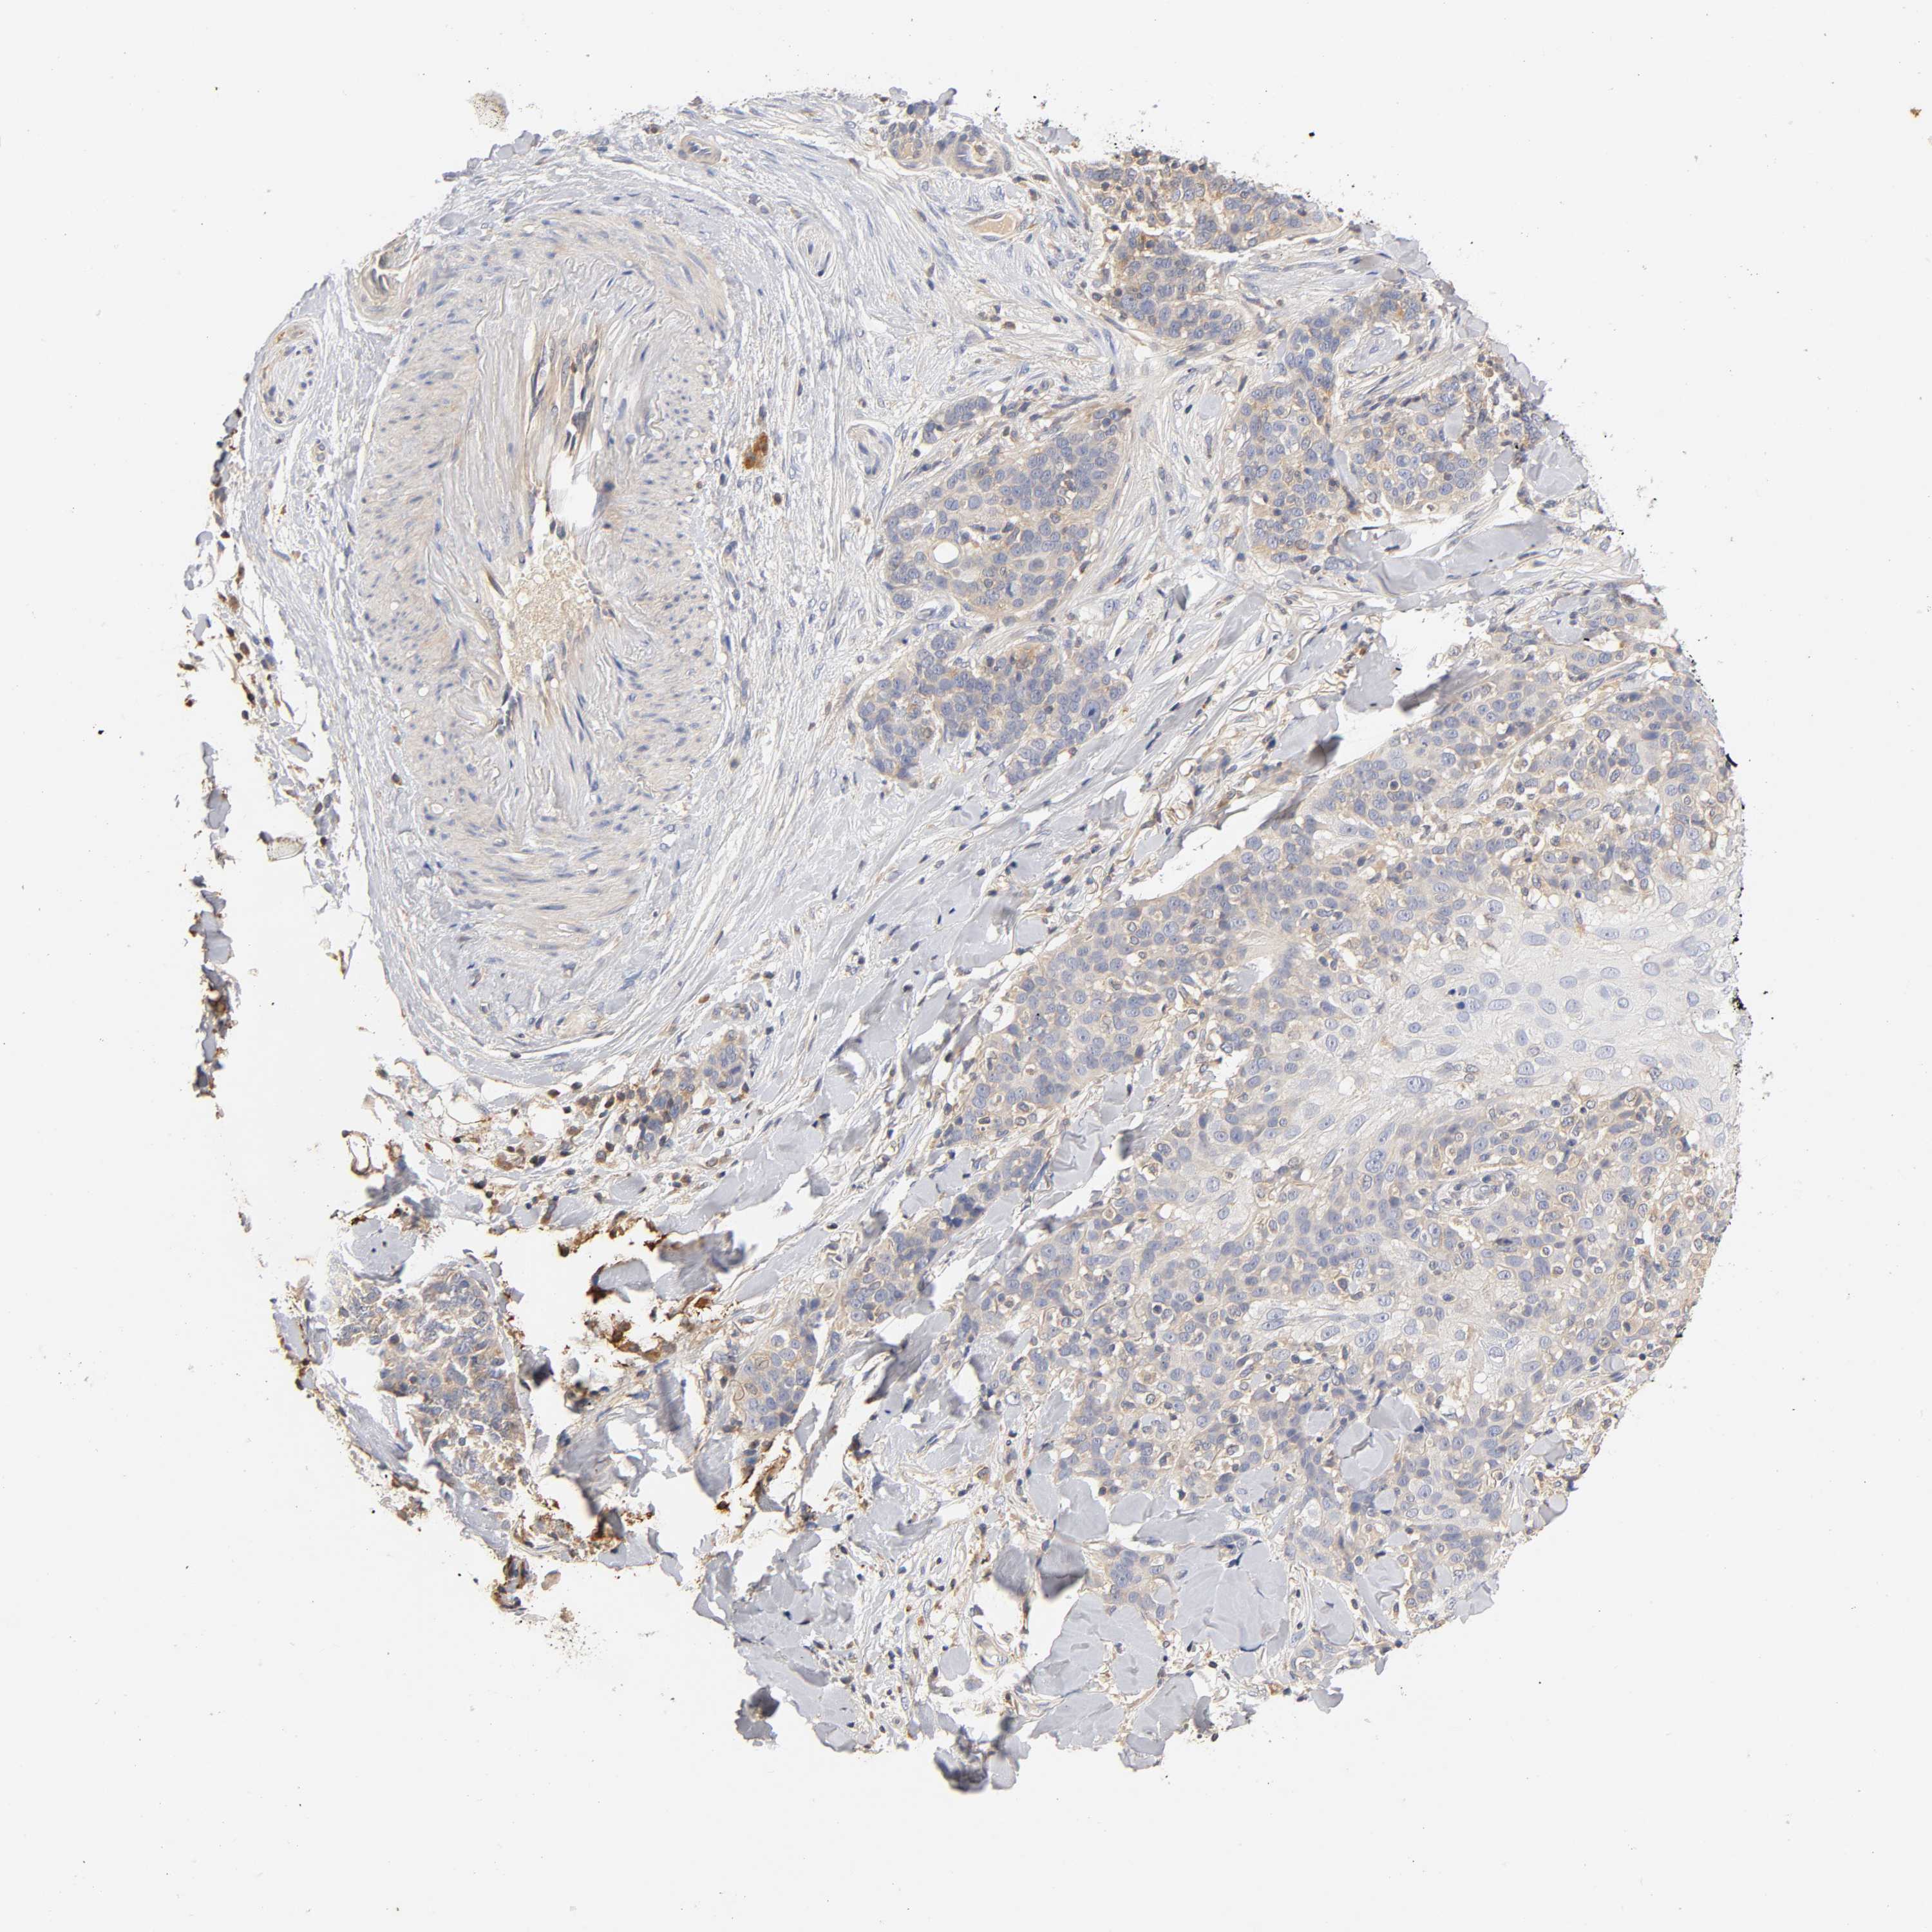

SKIN CANCER - Protein expressioni

A mouse-over function shows sample information and annotation data. Click on an image to view it in a full screen mode. Samples can be filtered based on level of antibody staining by selecting one or several of the following categories: high, medium, low and not detected. The assay and annotation is described here.

Antibody stainingi

Antibody staining in the annotated cell types in the current human tissue is reported as not detected, low, medium, or high, based on conventional immunohistochemistry profiling in selected tissues. This score is based on the combination of the staining intensity and fraction of stained cells.

Each image is clickable and will lead to virtual microscopy that enables deeper exploration of all samples and also displays staining intensity scores, fraction scores and subcellular localization as well as patient and tissue information for each sample.

Antibody CAB005052

Squamous cell carcinoma, NOS

Basal cell carcinoma